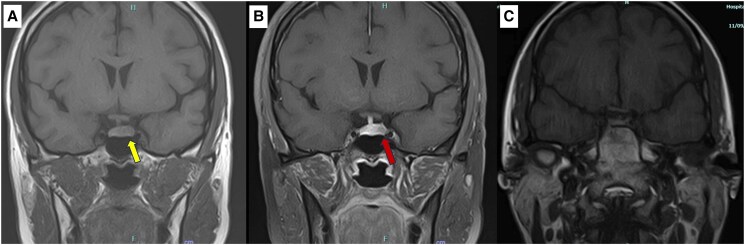

周期性库欣综合征(CS)是一种罕见的CS,以间歇性高皮质醇血症为特征。我们报告一例30岁女性被诊断为acth依赖性库欣病,经初步生化检查和垂体成像证实。虽然计划进行手术,但她经历了几个月的自然缓解,随后怀孕,随后在产后早期复发。经蝶窦切除左侧垂体腺瘤,确认为促肾上腺皮质激素分泌瘤。对文献的回顾显示,该病例增加了周期性CS患者的数量,特别注意孕期高皮质醇症的诊断挑战。虽然有文献记载垂体手术后产后立即复发库欣病的病例,但这是首次报道的产后早期复发的循环CS病例。本病例强调了长期随访对高怀疑指数的周期性CS患者的重要性,以及在妊娠和围产期期间管理病情的诊断挑战。

Cyclic Cushing syndrome (CS) is a rare form of CS characterized by intermittent episodes of hypercortisolism. We report the case of a 30-year-old female who was diagnosed with ACTH-dependent Cushing disease, confirmed by initial biochemical tests and pituitary imaging. Although surgery was planned, she experienced spontaneous remission for several months, followed by pregnancy, and subsequently relapsed in the early postpartum period. Transsphenoidal resection of a left-sided pituitary adenoma was then performed, confirming an ACTH-secreting tumor. A review of the literature revealed that this case contributes to the increasing number of patients with cyclic CS, with particular attention to the challenges of diagnosing hypercortisolism during pregnancy. While cases of Cushing disease recurrence after pituitary surgery in the immediate postpartum period have been documented, this is the first reported case of early postpartum relapse in cyclic CS. This case highlights the importance of long-term follow-up in patients with a high index of suspicion for cyclic CS, as well as the diagnostic challenges in managing the condition during pregnancy and the peripartum period.